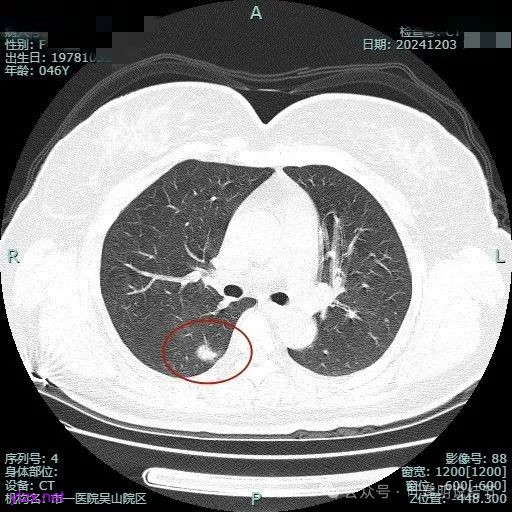

时间很快到了2025年3月,结友又来我门诊复查,我还以为她在别处开了刀了呢,结果并没有,说是与家人商量后决定吃中药三个月看看能不能好。我们来看看再复查的情况,中药有没有起作用:

总体感觉三处病灶边缘的淡磨玻璃成分好转不太明显了,实性成分较前略显致密点,大小与形态是说不上显著变化的。所以有几点可以肯定:1、消炎没有效;2、中药没有用;3、考虑多原发肺癌,且为浸润性腺癌可能性大些,得手术!